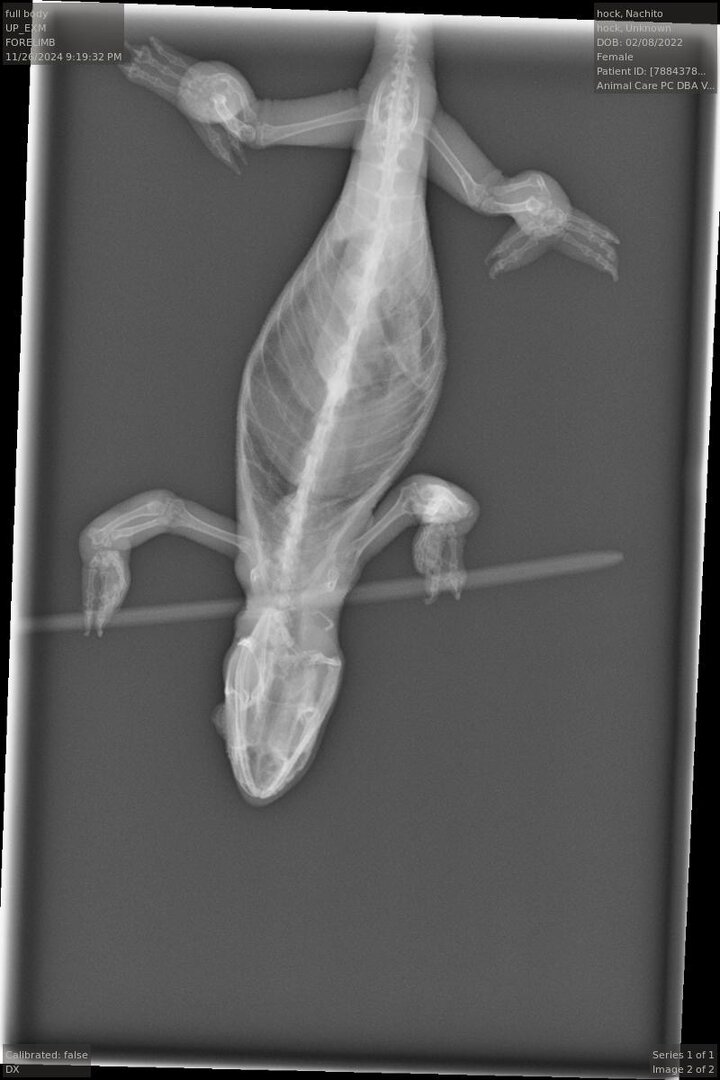

! But today at a vet appointment, Nachito was finally diagnosed with gout. After months of her uric acid levels seeming to be normal, today they came back as elevated.

Other than the uric acid levels and pore, the vet said there was nothing else significant on the X-rays and ultrasound.

Anyway! I’m hoping to get an email of the X-rays to share! If anyone has any more advice on gout or anything similar, it is welcome! Thanks for all the support as always!